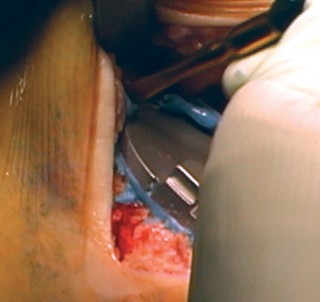

الخطوة 3: قطع عظم الساق (Tibial Cut)

- الدليل خارج النخاع (Extramedullary Guide): يُستخدم دليل خارج النخاع لقطع عظم الساق.

- إزالة الرباط الصليبي الأمامي (ACL): يتم قطع الرباط الصليبي الأمامي من موضع ارتباطه.

- تحريك الساق للأمام: تُحرك الساق للأمام (subluxed) لزيادة كشف الجزء العلوي من عظم الساق.

- وضع الدليل: يُوضع الدليل خارج النخاع فوق الثلث الإنسي من الحدبة الظنبوبية، بمحاذاة عرف الساق، وفي مركز مفصل الكاحل.

- تحديد الميل: يُحدد الميل المناسب ويُثبت الدليل في مكانه.

- القطع والحماية: تُحمى الأربطة الجانبية بالمبعدات، ويُقطع عظم الساق بشكل عمودي على محوره.

-

اعتبارات هامة (Pitfalls):

- يجب تجنب القطع المائل لعظم الساق (varus cut) بأي ثمن. يرتبط القطع المائل لعظم الساق في أي عملية استبدال مفصل الركبة بزيادة معدلات الفشل، خاصة في المرضى الذين يعانون من السمنة المفرطة. يحرص الأستاذ الدكتور محمد هطيف على الدقة القصوى لتجنب هذا الخطر.